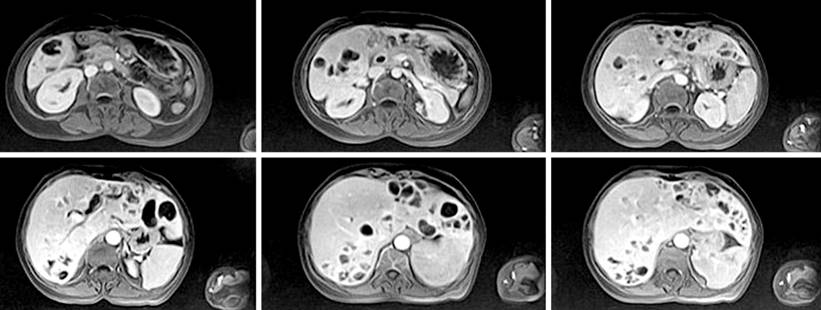

In the last five years, she was evaluated in different health centers, reporting laboratory studies, digestive screening (universal erythematous gastropathy, with Helicobacter pylori +), and colonoscopy without pathological findings. In addition, an abdominal resonance was performed, obtaining axial and coronal planes in T2, T1, T2FAT-SAT, FASE, and FS images, with and without contrast medium. They showed an enlarged liver and preserved morphology, with multiple cystic lesions randomly distributed in both liver lobes and an annular enhancement of the contrast medium (Figure 1). Magnetic resonance cholangiography was also performed, which revealed significant dilation of the intrahepatic bile duct, specifically the left one, and a well-defined cystic lesion with regular borders, which caused dilation of the extrahepatic bile duct (Figure 2). After injection of the contrast medium, a filling defect was observed, suggesting choledocholithiasis in the left hepatic duct. A biopsy was performed that did not report findings suggestive of malignancy, so we decided to manage the acute clinical picture with antibiotic therapy (carbapenems) only and periodic follow-up of the lesion.